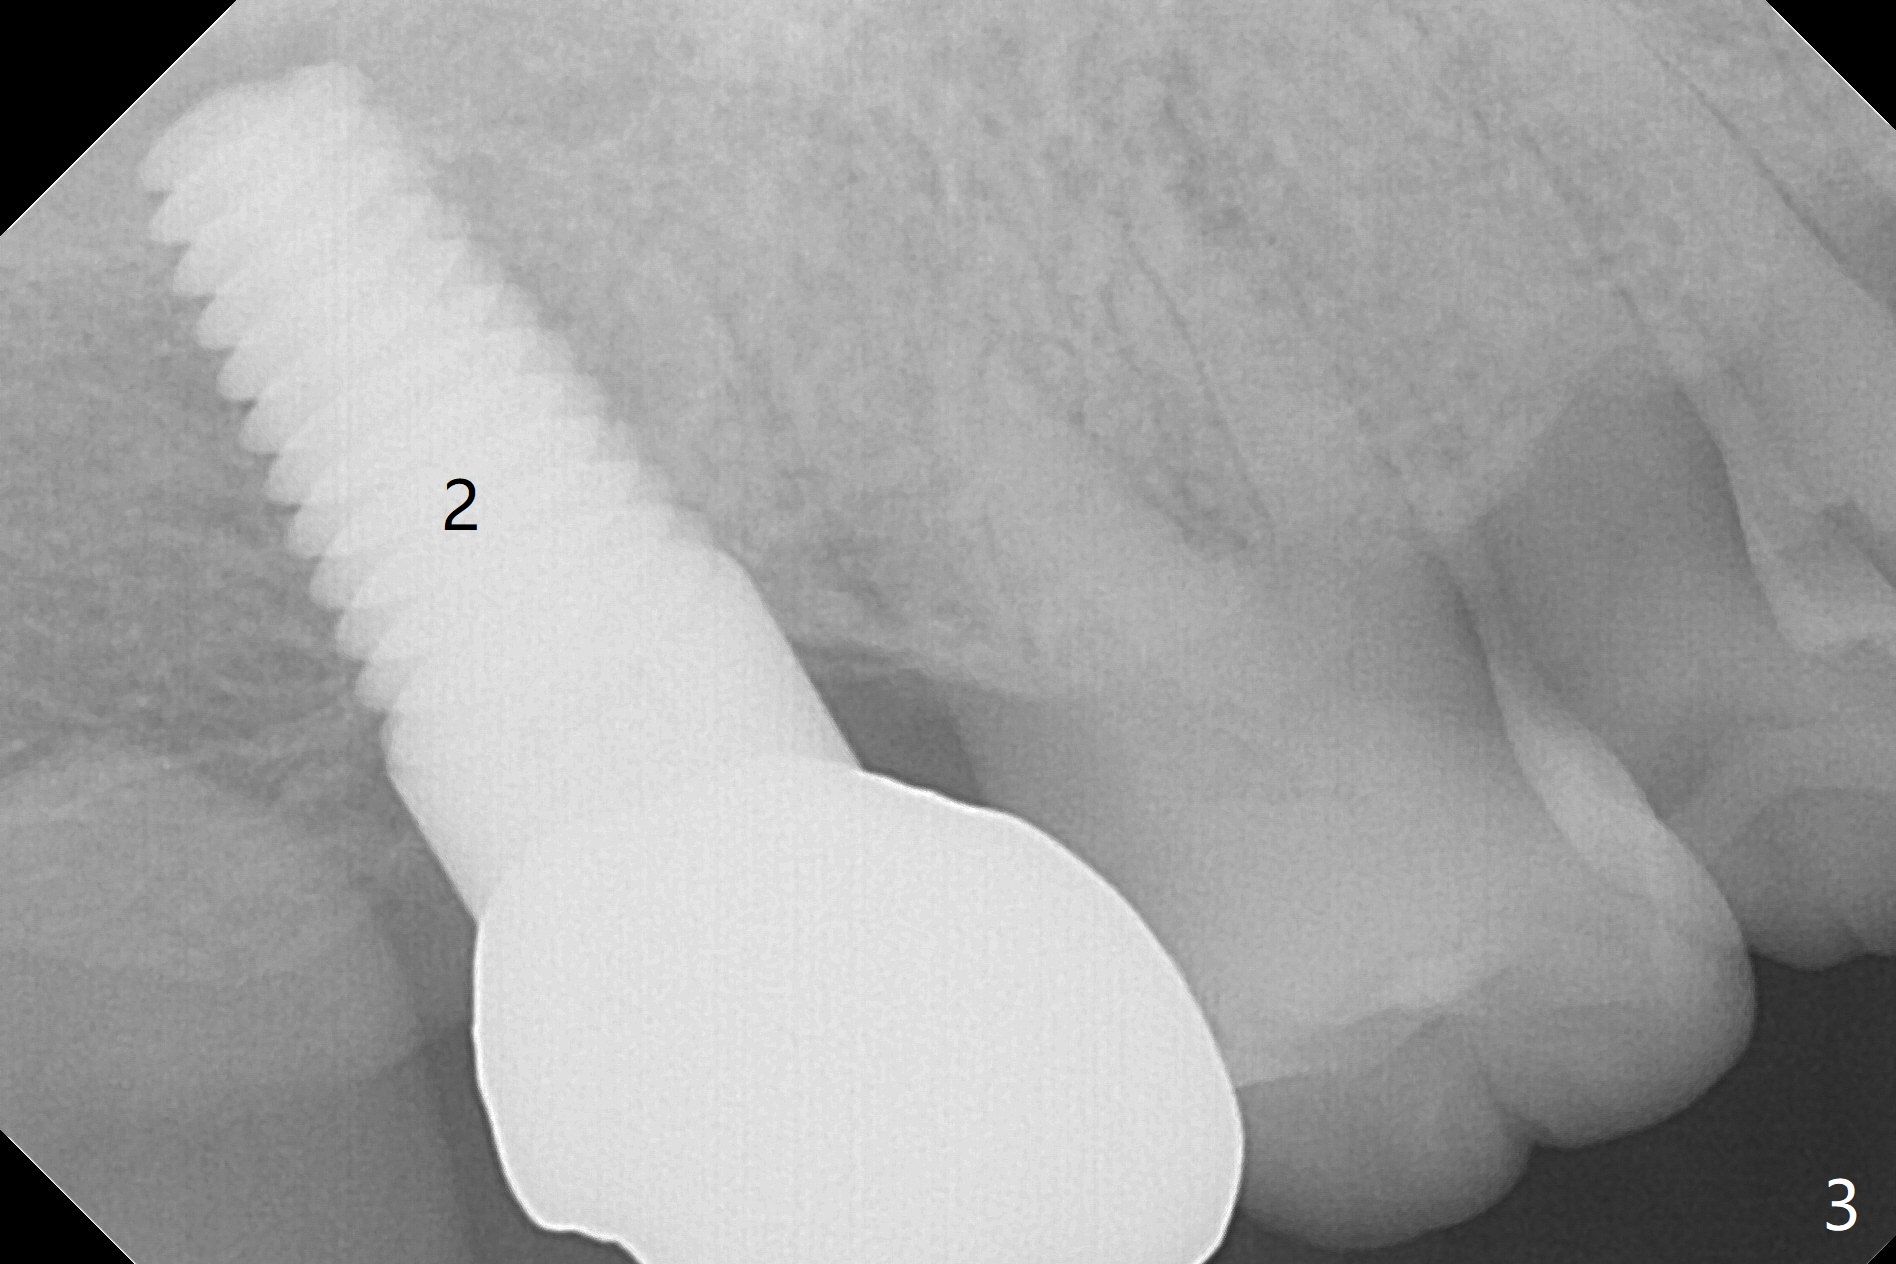

A 76-year-old man initially (3 years ago) presented to clinic for implant consultation 2 weeks after #2 extraction due to root canal failure. A 7x17 mm tissue-level implant was placed following bone expansion and tapping ~ 4 weeks post extraction. A 6x3 mm unipost was placed for immediate provi-sional. Impression was taken with retightening the unipost (no cementation) 3 months postop. Two weeks post cementation, the patient started to report food impaction at #18 crown (Fig.1). Eight months later, distal open margin was found; the tooth #3 seems to have occlusal trauma. Ten months later, #2 and 3 contact remains normal. Finally the crown at #18 was redone. ~1.5 years post cementation, #2 crown proximal contact becomes loose. The crown was redone with no occlusal contact. Retrospectively it is due to mesial shifting of the tooth #3. Nine months post cementation, the tooth #18 shows sign and symptom of root fracture (Fig.2). Antibiotic appears to alleviate the pain. Occlusal adjustment is done at #30 pontic to reduce trauma to #3 with symptom improvement (Fig.3).

In all, the patient should be a heavy bruxer. When extraction and immediate implant is done at #18, immediate provisional should be low and stable (keep bone graft in place). It appears that a temporary abutment can accomplish the purpose. An IS one has been trimmed. There are 2 options for implant placement: along the long axis of the socket (Fig.4 using taps for osteotomy) and in the mesial slope of the socket (Fig.5 using drills). If the bone level implant (tap) does not work, switch to tissue level one (Fig.6).